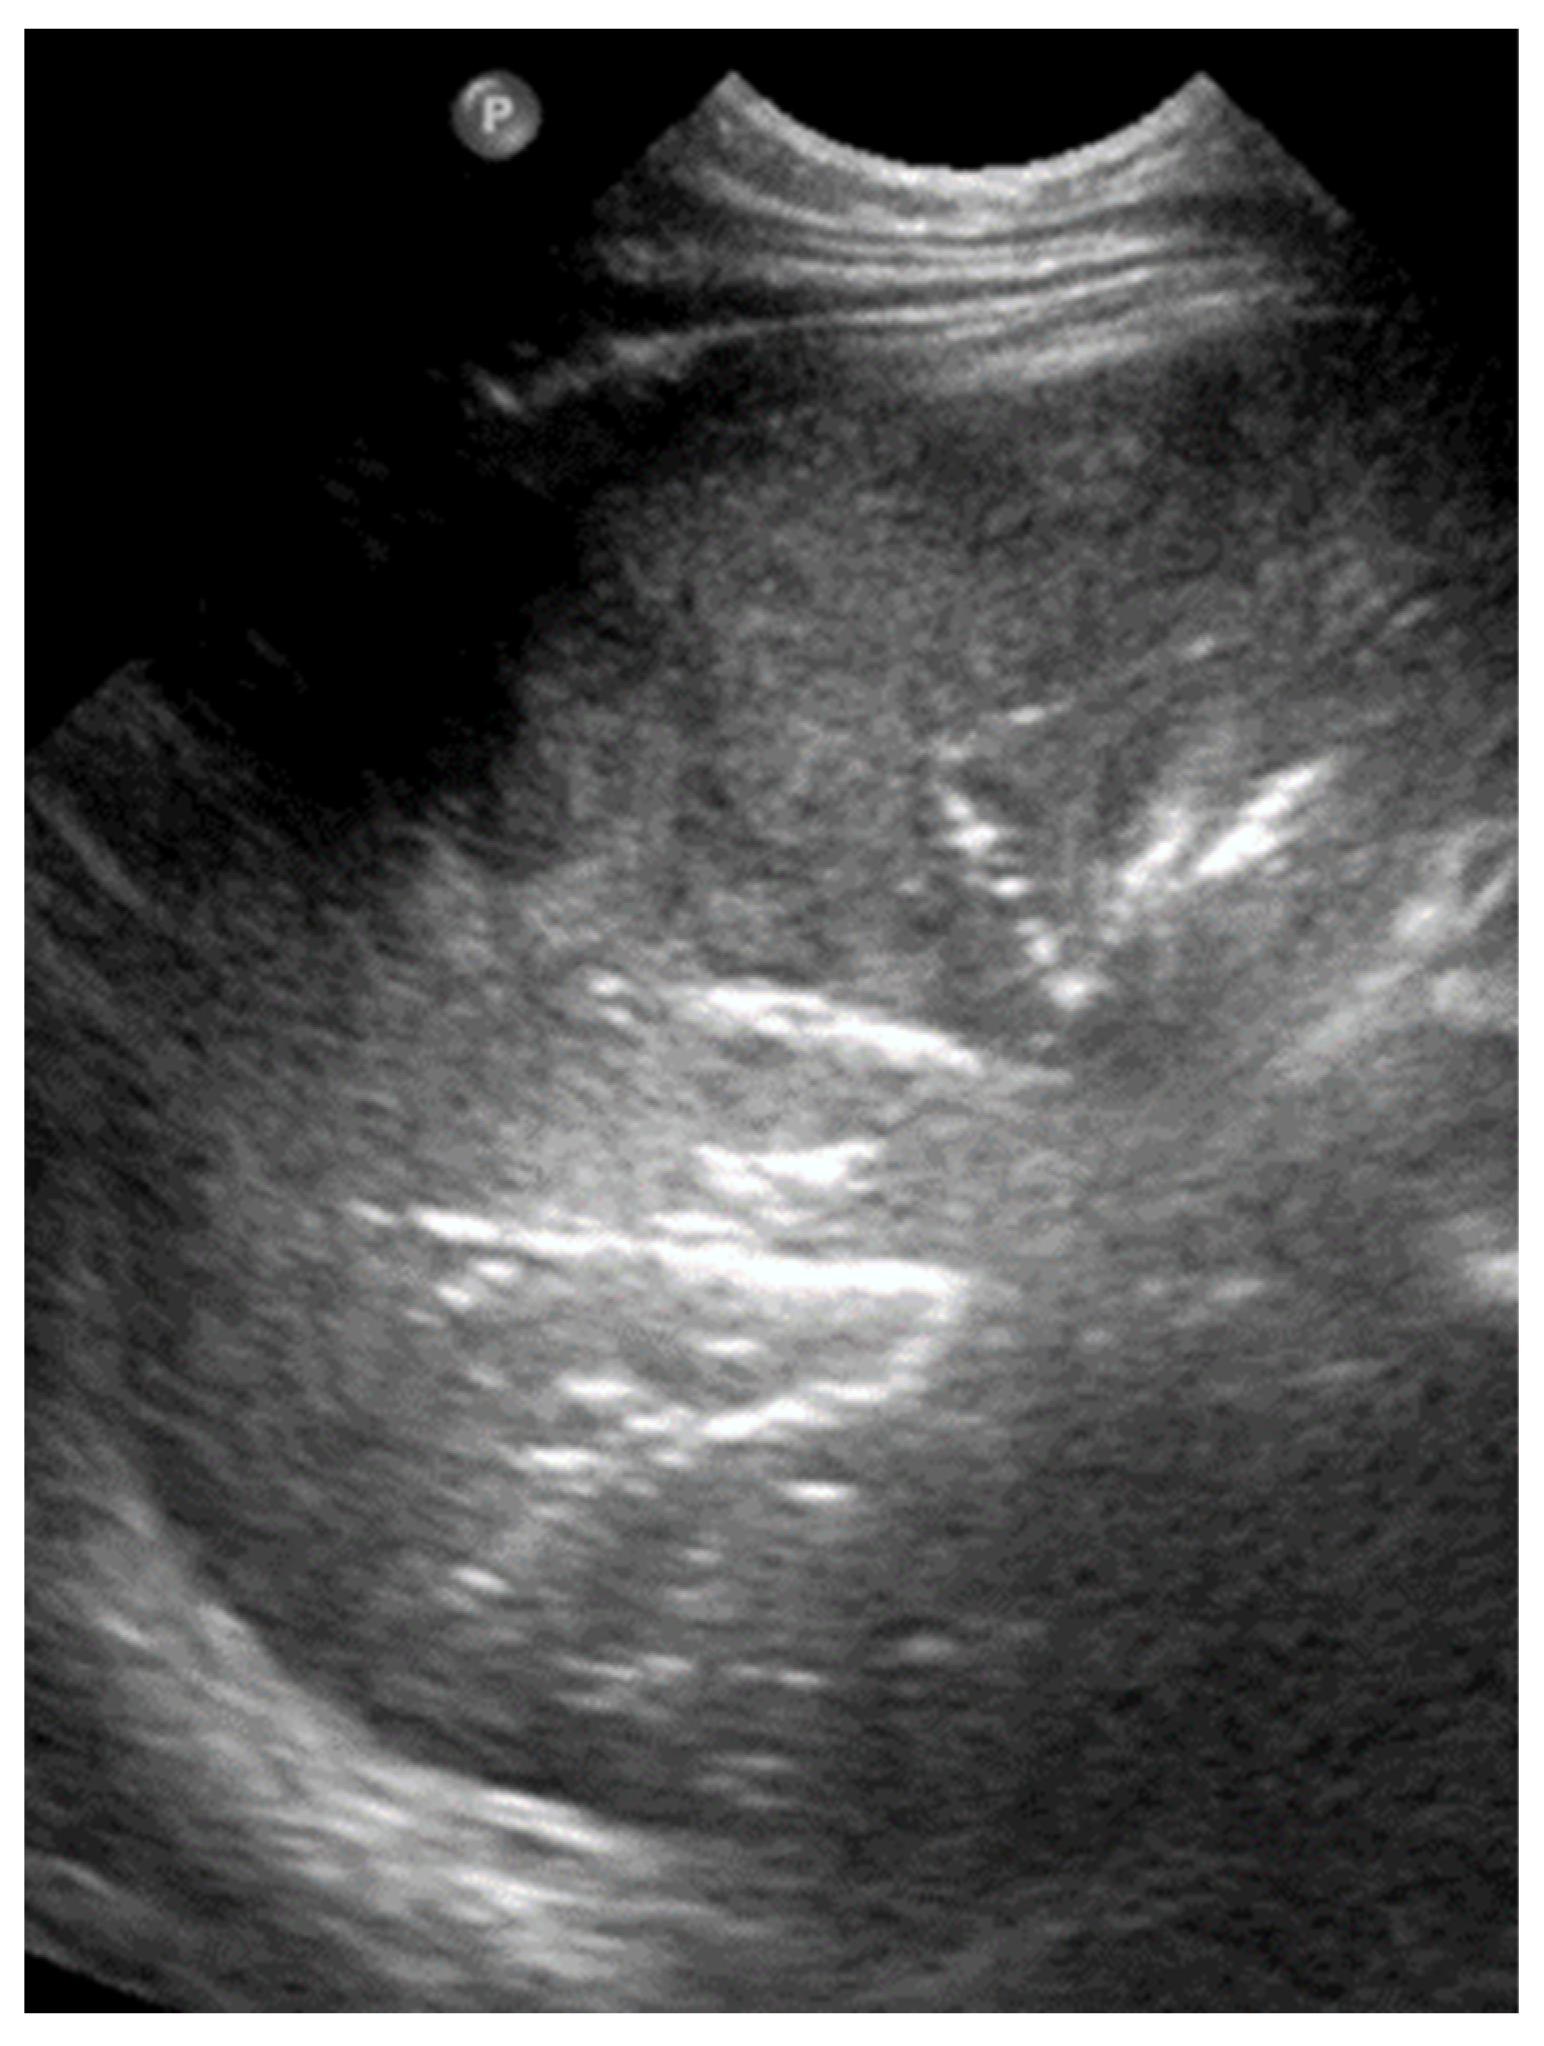

3.2.11. Empyema